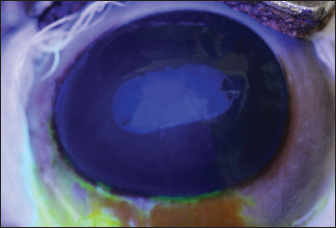

The study was approved by the Research of Committee of the Federal University of Rio Grande do Sul. The eyes were donated by a local slaughterhouse. Twenty eyeballs from 10 Brangus breed male bovines aged 24 months were studied. Enucleation was made immediately after slaughtering, and the eyes were labeled and stored in a moist chamber until analysis under a specular microscope. All ocular bulbs underwent an ophthalmic examination which included biomicroscopy with a slit lamp (Kowa SL-15, Nagoya, Aichi, Japan) (Fig. 1) and a fluorescein test (1% sodium fluorescein, Allergan, Sao Paulo, Brazil) (Fig. 2). Only healthy eyes were selected. Only eyes with transparent corneas and eyes with a negative fluorescein test were included in the study. All analyses were carried out within 4 hours after slaughter. For endothelial evaluation, a contact specular microscope (Celmax, Medical Service, Sao Carlos, Brazil) was used. All evaluations were carried out by the same examiner. After being removed from the wet chamber, the eyes were placed on a support adapted to the contact specular microscope and lubricated with ophthalmic eye drops (Lacri, carboxymethylcellulose). The objective lens of the specular microscope was positioned in the central region of the cornea, at a 90° angle between the evaluated structure and the device (Figs. 3 and 4). From each cornea, we obtained one micrograph, and 30 endothelial cells were analyzed in each image. Cell density was calculated using software coupled to the specular microscope (Celmax® specular microscope). Endothelial morphology was obtained through manual assessment of the number of sides of each cell. The values obtained were the means of each identified parameter.

Fig. 1. Slit lamp examination of a bovine eye.